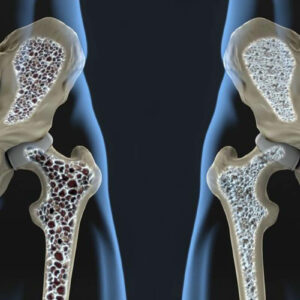

Things You Should Know about Bone Density Tests

As we age, our health gets worse and the list of medical tests we need to determine our current condition of health grows longer and longer. At times we tend to skip our tests because of our busy frame of mind, or because we think that we do not need them.